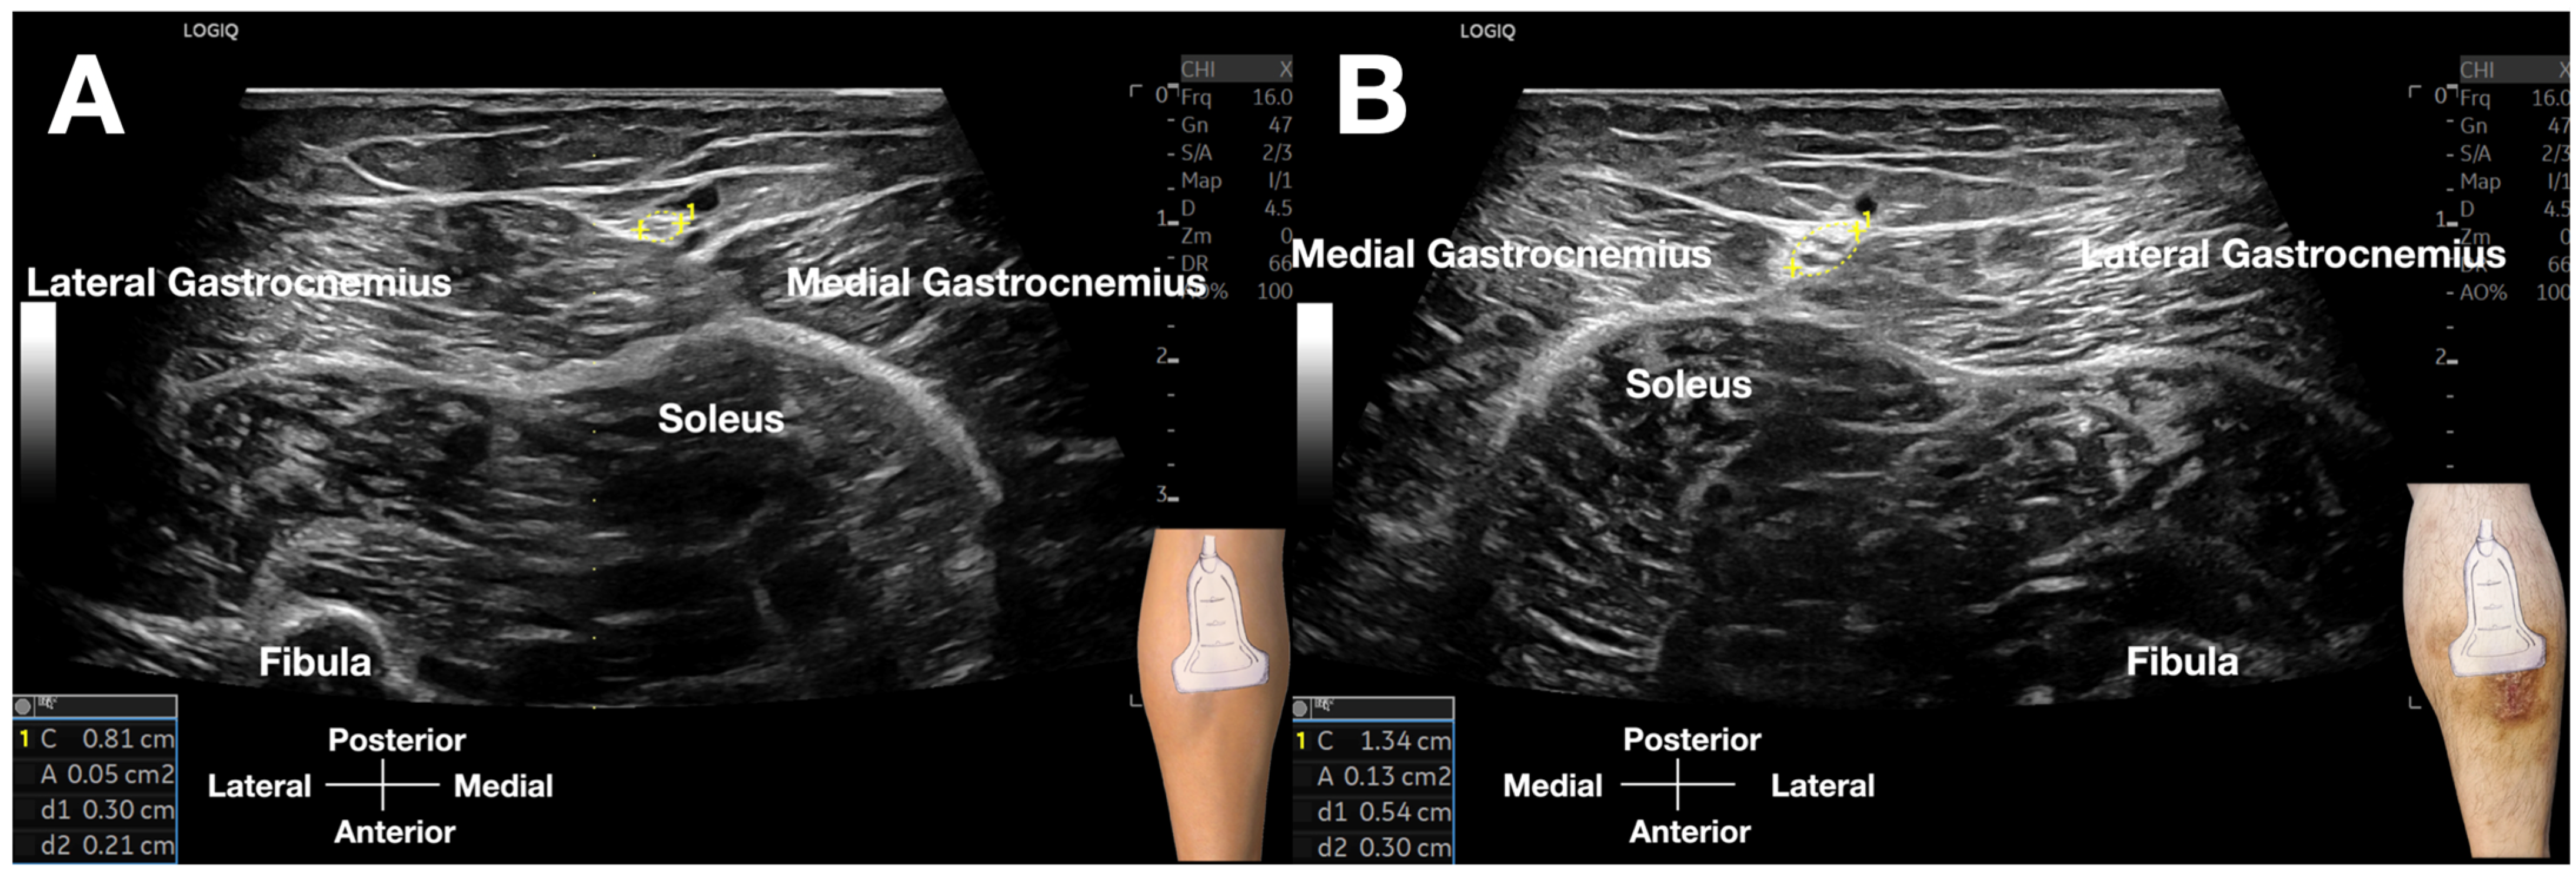

Figure 4.

Comparative cross-sectional ultrasound images of the sural nerve (SN). (A) Asymptomatic left leg: The SN (calipers) within the crural fascia’s fatty triangle demonstrates a normal cross-sectional area of 5 mm2, with preserved fascicular architecture and no perineural edema. (B) Symptomatic right leg: The SN (calipers) is significantly enlarged, with a cross-sectional area of 13 mm2, loss of fascicular definition, and surrounding hypoechoic edema, consistent with nerve pathology and fascial restriction.

The technique was executed with controlled digital pressure (estimated 2–4 kg/cm2) applied rhythmically for 10–15 s intervals at each assessment site, utilizing alternating lateral-to-medial and medial-to-lateral vectors (Figure 3, Video S1). Diagnostic interpretation followed a validated four-criterion protocol [3]: (1) Quantitative fascial mobility restriction (≤5 mm transverse excursion versus >5 mm contralaterally); (2) Precise reproduction of concordant Achilles pain upon sural nerve (SN) provocation; (3) Identification of crural fascial gliding impairment; (4) Sonographic evidence of significant nerve swelling, with a cross-sectional area (CSA) of 13 mm2 on the affected side, compared to 5 mm2 on the contralateral, asymptomatic side (Figure 4, Video S2), alongside perineural edema and fibrotic tissue changes.

Sonoguided Digital Palpation (SDP) represents a dynamic diagnostic technique integrating real-time ultrasonography with targeted layer palpation [3], grounded in established osteopathic principles of myofascial and visceral assessment [32,33,34,35,36,37,38]. This methodology enables direct visualization and quantification of tissue tension abnormalities and interfacial friction dynamics. In the present case, SDP was employed to evaluate the crural fascia (CF), wherein restricted gliding mobility relative to superficial adipose tissue or underlying gastrocnemius musculature signified fascial pathology (Figure 4 and Video S1). A critical advantage of this approach is the capacity for real-time contralateral comparison, providing an internal control for biomechanical assessment.